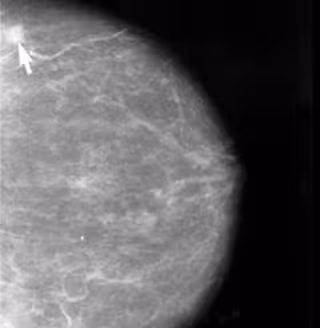

El ejercicio físico y la dieta mediterránea, fundamentales para prevenir el cáncer de mama

Cáncer de Mama